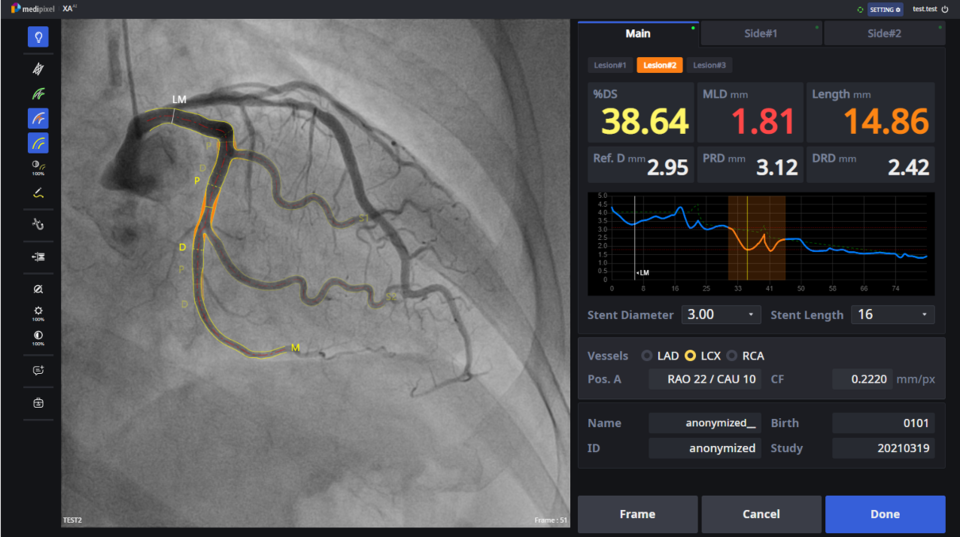

메디픽셀은 AI를 기반으로 심혈관질환의 진단과 치료를 위한 의료기기 소프트웨어(Software as a Medical Device, SaMD)를 개발하고 있습니다. 심혈관중재시술의 진단에는 두 가지 방법이 있습니다. 첫 번째는 혈관조영술(Angiography)을 눈으로 보고 심혈관 협착의 정도를 파악하는 방식으로 ‘형태적 진단’입니다. 형태적 진단은 시각적 평가이기 때문에 정확도가 매번 상이할 수 있으며, 의료진에 따라 편차가 발생하기도 합니다. 메디픽셀의 솔루션 ‘MPXA’는 AI와 컴퓨터 비전 기술을 활용합니다. 심혈관 조영 영상을 분석해 병변을 찾고, 혈관이 막힌 정도를 수치로 정량화해 제시합니다. 이 모든 결과는 시술 도중에 실시간으로 제공되기 때문에 의료진의 형태적 판단에 결정적이고 유익한 도움을 줄 수 있습니다. MPXA 제품은 2021년 말 국내 식품의약품안전처, 지난 3월 미국 식품의약국(FDA) 인증을 받은 바 있습니다. 심혈관중재시술의 두 번째는 ‘기능적 진단’으로, 와이어 형태의 FFR 디바이스를 병변 부위에 삽입해 실제로 혈류가 얼마나 원활하게 흐르고 있는지 평가하는 방식입니다. 많은 논문에 의하면 기능적 진단이 형태적 평가보다 더욱 정확할 수 있다는 사실이 검증된 바 있습니다. 이에 기능적 진단은 우리나라와 미국 등 의료 선진국의 가이드라인에 의해 진료표준(Standard of Care, SoC)으로 인정받고 있는 진단 방식입니다. 하지만 진단에 걸리는 시간∙비용, 환자에게 불편함을 유발하는 약물 사용 등의 제약으로 실제 현실에서의 사용률은 높지 않습니다. 이에 반해 메디픽셀의 ‘FFRXA’는 기존의 제약사항은 회피하면서도 성능은 더욱 우수한 제품으로 개발됐습니다. 심혈관 조영 영상 2장을 결합해 3D 모델링 작업을 거친 후, 이를 기반으로 소프트웨어 알고리즘을 통한 기능적 진단이 가능한 제품입니다.